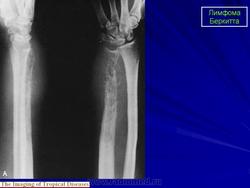

В диагностике лимфомы Беркитта гистологическое исследование опухоли играет большую роль. Под микроскопом видно множество мелких темных лимфоцитов периодически перемежается крупными «звездами» - макрофагами, которые пытаются фагоцитировать опухолевые клетки ( так называемое « звездное небо» ). Другими диагностическими методами исследования, в зависимости от предполагаемых очагов локализации опухоли, являются: двусторонняя биопсия и аспирация костного мозга; рентгенография органов грудной клетки, брюшной полости и таза, реже - двусторонняя лимфоангиография нижних конечностей и таза; рентгенография костей, биопсия печени.

Приложения:

1.lim_.slayd51.jpg2.lim_.slayd52.jpg